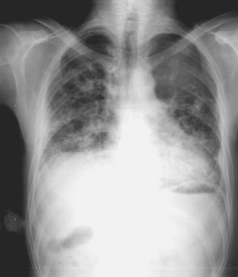

Moreira et al. (2010), acompanharam um paciente de 27 anos, que trabalhava há 8 anos como afiador de ferramentas de metal-duro (serra, serrotes e facas de corte), trabalhava por oito horas diárias, equivalente a 40 horas semanais, sem o uso do EPI, ou EPR -equipamento de proteção respiratória. Esse profissional utilizava no processo de retificação/afiação um rebolo diamantado sintético, em um ambiente fechado. Baseado na história desse trabalhador, nos exames de imagem (radiografia de tórax) e no exame anatomopatológico, foi feito o diagnóstico de pneumoconiose por metal-duro ou fibrose pulmonar. O tratamento da pneumopatia por exposição a metal-duro envolve o afastamento completo da exposição ao agente nocivo e corticoterapia em doses altas. Quando já existe fibrose pulmonar extensa, uma apresentação de estudo de caso raro, não há significativa resposta ao tratamento.